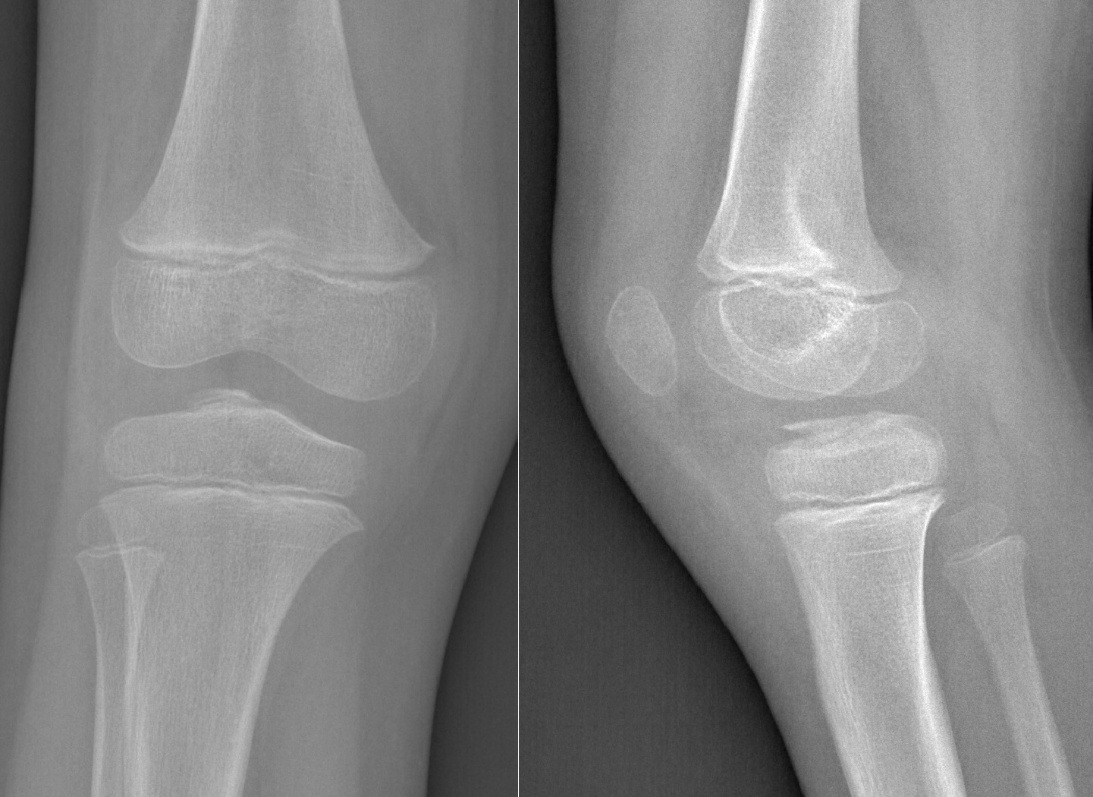

At the 30-day follow-up, clinical evaluation showed resolution of pain and a stable knee on examination. Radiographs performed at the same time confirmed satisfactory healing of the avulsion fracture (Figure 4).